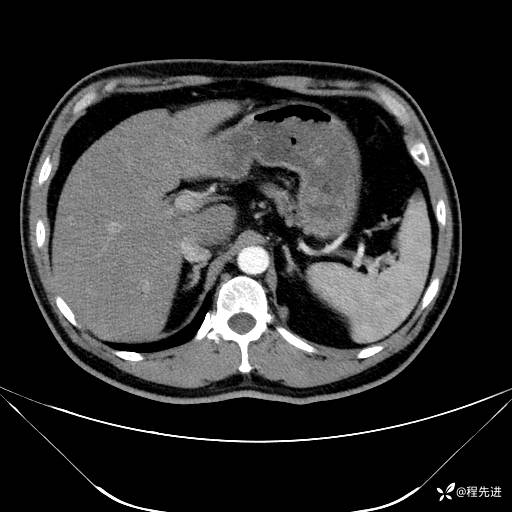

【腹盆】特别精彩病例|发现腹膜后肿物1月余

主诉:发现腹膜后肿物1月余

现病史:患者1月余前查体,行超声检查提示:后腹膜囊实性肿块;慢性胆囊炎伴胆囊内结石;无腹痛腹胀,不伴腹泻发热等;偶感腰背部酸痛。

CT平扫+增强: